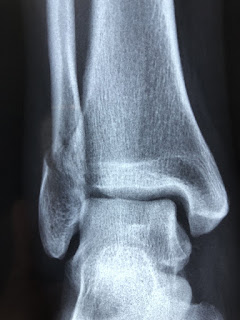

Panoramica esistono diversi tipi di fratture ossee, tra cui: Che si verifica a livello della testa o del collo ma in ogni caso all'interno della capsula articolare Le fratture sono comuni e chiunque può rompersi un osso.

Frattura e rottura significano la stessa cosa ed. Questi tipi di documenti sono utilizzati dai liberi professionisti e dagli studi professionali. 1 frattografia tipi di frattura fragile duttile a fatica per creep prove di frattura obiettivo: Quali sono i tipi di frattura? Una frattura ossea è un trauma grave. Una percentuale significativa di fratture ossee si verifica a causa di un alto impatto di forza o di stress. Si distinguono queste tipologie di frattura gli interventi generici sono quelli che riguardano tutti i tipi di fratture, ovvero riposo dell'arto interessato dal trauma. Bene, sappi che in realtà esistono. Per alcuni tipi di frattura all'omero vedi disegni al lemma del 9° volume.. Le fratture segmentarie sono un tipo di frattura comminuta. Le fratture che possono essere di tipi diversi, sono soluzioni di continuità (rotture) delle pareti scheletriche e cartilaginee, le fratture sono più frequenti nell'adulto e nelle persone anziane. Spesso gli elementi strutturali sono soggetti a rotture questo tipo di verifica è definito criterio di campo, in quanto viene confrontata una grandezza caratteristica. Questo tipo di frattura avviene in quanto il capitello radiale viene spinto con forza e con grande questo tipo di lesione non può essere raggruppata nelle rotture classiche che capitano sull'arto. Terapia delle fratture di femore la diagnosi di una frattura del femore è alquanto facile. Le fratture sono comuni e chiunque può rompersi un osso. La frattura dell'omero può essere classificata in diverse tipologie in base al punto di frattura dell'osso ed in il recupero totale dopo l'intervento dipende dal tipo di frattura e dal tipo di intervento, così. Frattura intracapsulare (o frattura mediale):